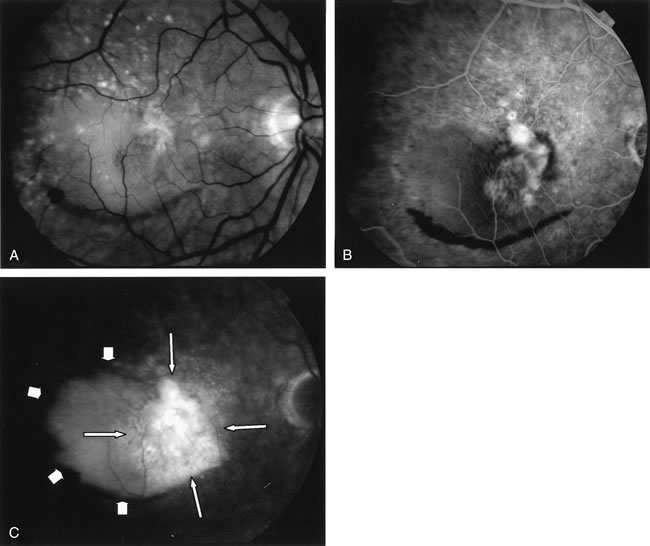

Trauma can induce a wide spectrum of alterations of the retina, RPE, and choroid. Most types of traumatic maculopathy, such as Purtscher's retinopathy, Berlin's edema, retinal contusion, traumatic macular hole, and choroidal rupture, are readily apparent on clinical examination.257 Choroidal rupture, althoughe usually evident clinically, may be more obvious on FA (Fig. 39). Contusion necrosis of the RPE may present clinically with an associated RPE detachment, an overlying neurosensory detachment, and a subtle change in RPE pigmentation. FA can demonstrate the site of leakage into the subretinal space, unless the RPE defect has healed by the time of testing. FA is particularly helpful in differentiating retinal concussion (Berlin's edema), in which FA findings are normal, from retinal contusion, in which there is RPE damage and, consequently, increased transmission of choroidal fluorescence on FA.257 In Purtscher's retinopathy, FA can document vascular closure, which accounts for the retinal infarctions (Fig. 40).258

Fig. 39. Choroidal rupture. A large choroidal rupture arcs circumferentially over the optic nerve head (arrow). The hyperfluorescence is from scleral staining that is easily visible through this defect of the retinal pigment epithelium, Bruch's membrane, and choriocapillaris. There is blocked fluorescence where laser treatment has obliterated a choroidal neovascularization that developed at the inferior aspect of the defect. (Courtesy of Dr. Kenneth G. Noble.)

Fig. 40. Purtscher's retinopathy. A. Red-free photograph demonstrates retinal whitening owing to ischemia/infarction. This patient had sustained a severe blunt chest injury in an automobile accident. B. Fluorescein angiogram demonstrates nonperfusion of the retinal capillaries, particularly in the perifoveal area. (Courtesy of Dr. Kenneth G. Noble.)